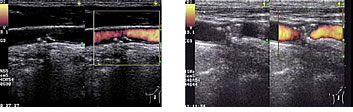

頸動脈狭窄があるか否かは、外来の超音波検査(エコー検査)ですぐにわかります。高度な狭窄が疑われたり、超音波検査で判定が困難な場合には、さらにMRA検査や3次元CTを追加することもあります。

超音波検査の際は、ベッドに横になり、頸部に専用のゼリーをつけて、超音波の送受信機(プローベ)を当てるだけです。多少圧迫感はありますが、痛みは全くなく、5-15分ほどで検査は終了します。放射線を用いていないので、たとえば妊娠中の方にも安全に行うことができ、MRI検査のように閉所でじっとしている必要もありません。結果はその場でわかります。いずれにしても外来で簡単に検査が可能ですので、次の項に述べるような場合は、受診をお勧めします。

頸動脈超音波検査で発見された動脈硬化

(各図の右側の橙色は血流のある部位を示している)